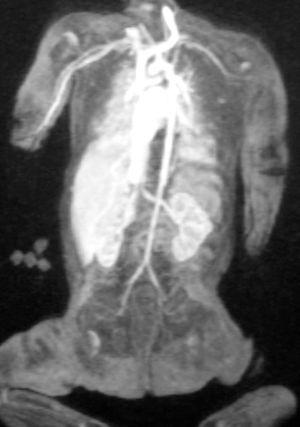

En la exploración física al nacimiento, se objetivó fenotipo sugerente de síndrome de Down. El análisis citogenético demostró trisomía 21. El ecocardiograma reveló una comunicación interventricular muscular pequeña y una comunicación interauricular moderada. La ecografía cerebral fue normal. Se realizó una ecografía abdominal donde se visualizó un hígado de tamaño y ecogenicidad normal con una vena porta de 0,17 cm unida a una vena suprahepática de 0,7 cm de diámetro que desembocaba en la vena cava inferior. La anastomosis entre la vena porta y la vena cava inferior se confirmó en la angiorresonancia magnética nuclear (figs. 1 y 2).

Figura 1.Angio-RM: anastomosis entre la vena porta y la vena cava inferior a nivel del hilio hepático.

Figura 2.Angio-RM: vena cava inferior retrohepática marcadamente dilatada hasta su entrada en la aurícula derecha. Leve disminución de calibre de la aorta abdominal.